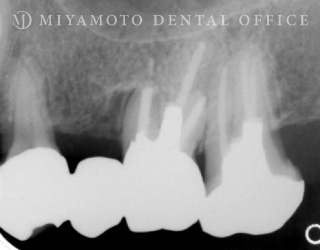

症例15

リグロス®を用いた歯周組織再生療法(根分岐部)+歯内療法

1. 治療前

2. 治療後